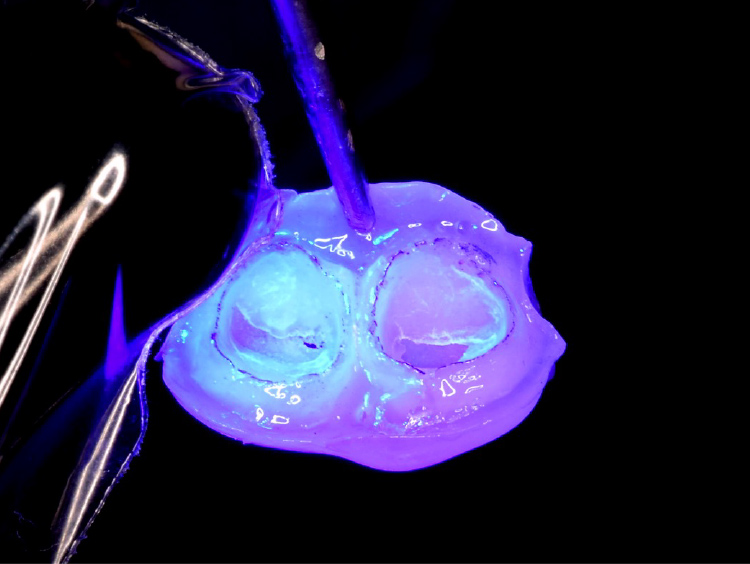

写真に示されているのは、当院独自の【隔壁テック】と呼ぶ手法です。これは、治療中の前歯が外見上、治療を行っていることが分かりにくいよう工夫されたものです。